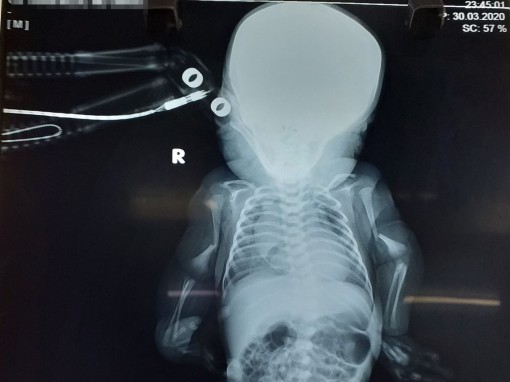

Phát hiện trẻ sơ sinh mắc bệnh xương thủy tinh rất hiếm gặp

(CTO) - Các bác sĩ Khoa Nhi - Sơ sinh Bệnh viện Phụ sản TP Cần Thơ vừa phát hiện một trường hợp bé trai sơ sinh mắc bệnh xương thủy tinh,